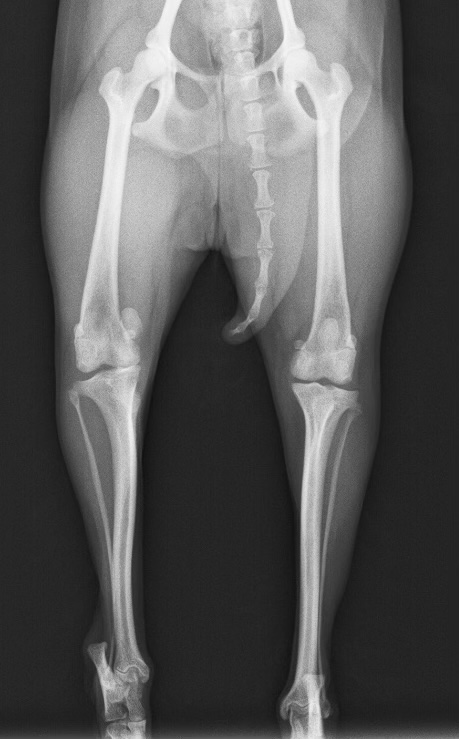

・右膝:膝蓋骨内方脱臼Grade3、クリック音(+)。明らかな痛みはないが、歩行時に脱臼すると右脚を挙上してぴょんぴょん跳ねる

・左膝:膝蓋骨内方脱臼Grade2

・レントゲン検査にて、右膝膝蓋骨の内方脱臼

膝蓋骨内方脱臼(Grade3)